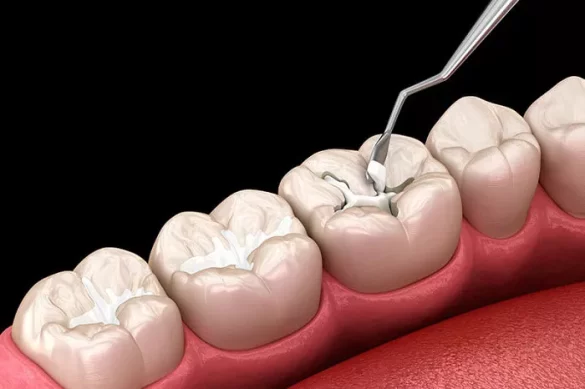

Composite Fillings

Composite resins are a popular choice, especially in modern dentistry. They consist of a combination of plastic and fine glass particles and are available in a wide range of tooth-colored shades.

Bonding Capability: Composite fillings chemically bond to the enamel and dentin of the tooth. This bonding not only helps in restoring the structural integrity of the tooth but also reduces the risk of microleakage, which can lead to secondary decay.

Minimal Tooth Preparation: Compared to amalgam fillings, composite fillings require less removal of healthy tooth structure. This is because they rely on the bonding process rather than just mechanical retention, thereby preserving more of the natural tooth.